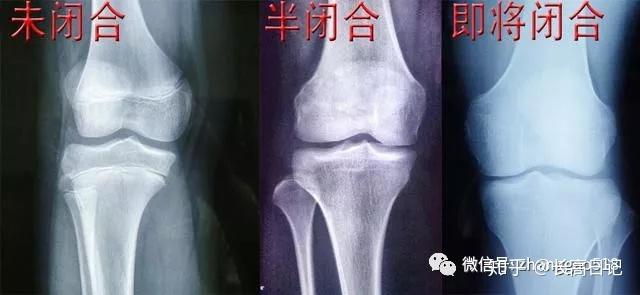

比尔高:怎么判断自己的骨骺线状态?

375x208 - 6KB - JPEG

简介:它随着年龄的增长而逐渐变短,当骨骺与干骺端的软骨完全骨化后,就形成一条紧密的缝,此时骨骺线完全闭合

答:多数情况下,只要骨骺线未闭合,还有长高的机会。 那么什么是骨骺线呢?看完下面这张图,你肯定能明白。 孩子婴幼儿时期,长骨的骨干和骨骺之间,存在一个软骨带。在X线片中

答:朋友你好,根据你的描述,你的骨骺线已闭合了。骨骺与干骺端之间的软骨,在幼儿的x光片上表现为一条较宽的透光带,它随着年龄的增长而逐渐变短,当骨骺与干骺端的软骨完全骨